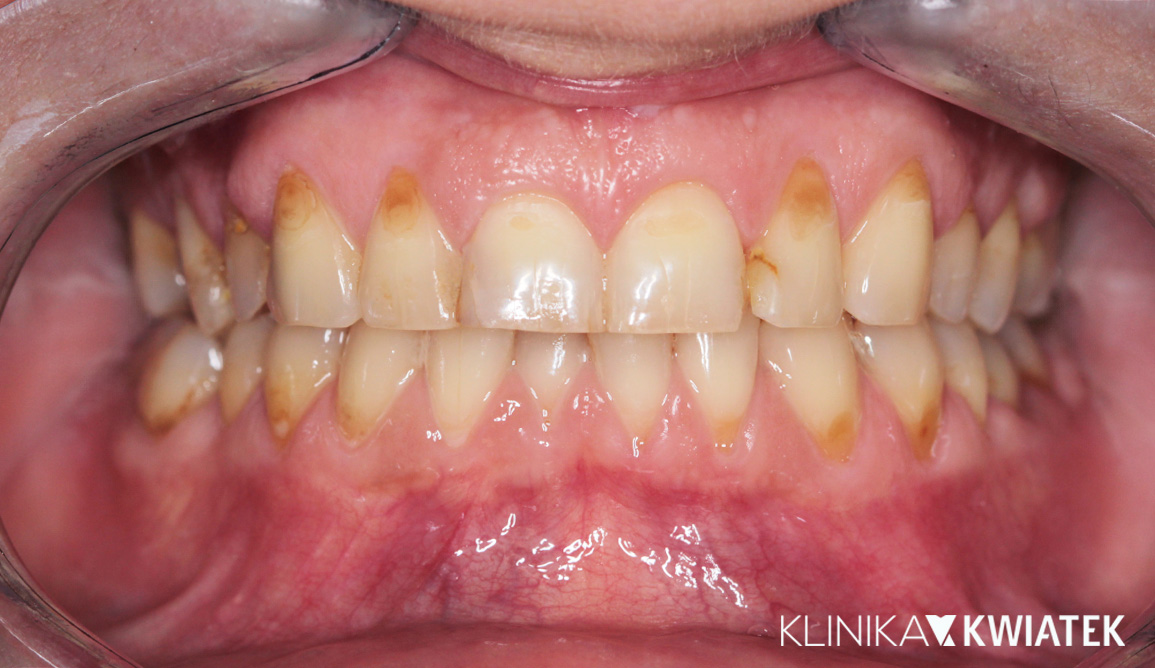

Pacjentka zgłosiła się z licznymi ubytkami, znacznym starciem zębów oraz objawami przeciążenia zgryzu wynikającymi z wieloletniego zaciskania i zgrzytania. Po pełnej diagnostyce przeprowadzono higienizację, leczenie zachowawcze, endodontyczne i szynoterapię, a następnie ortodoncję oraz finalną odbudowę estetyczno-protetyczną wszystkich startych powierzchni zębów. Efektem jest stabilny, zdrowy zgryz, prawidłowa praca stawów oraz harmonijny, trwały i estetyczny uśmiech Pacjentki.

PRZED

PO